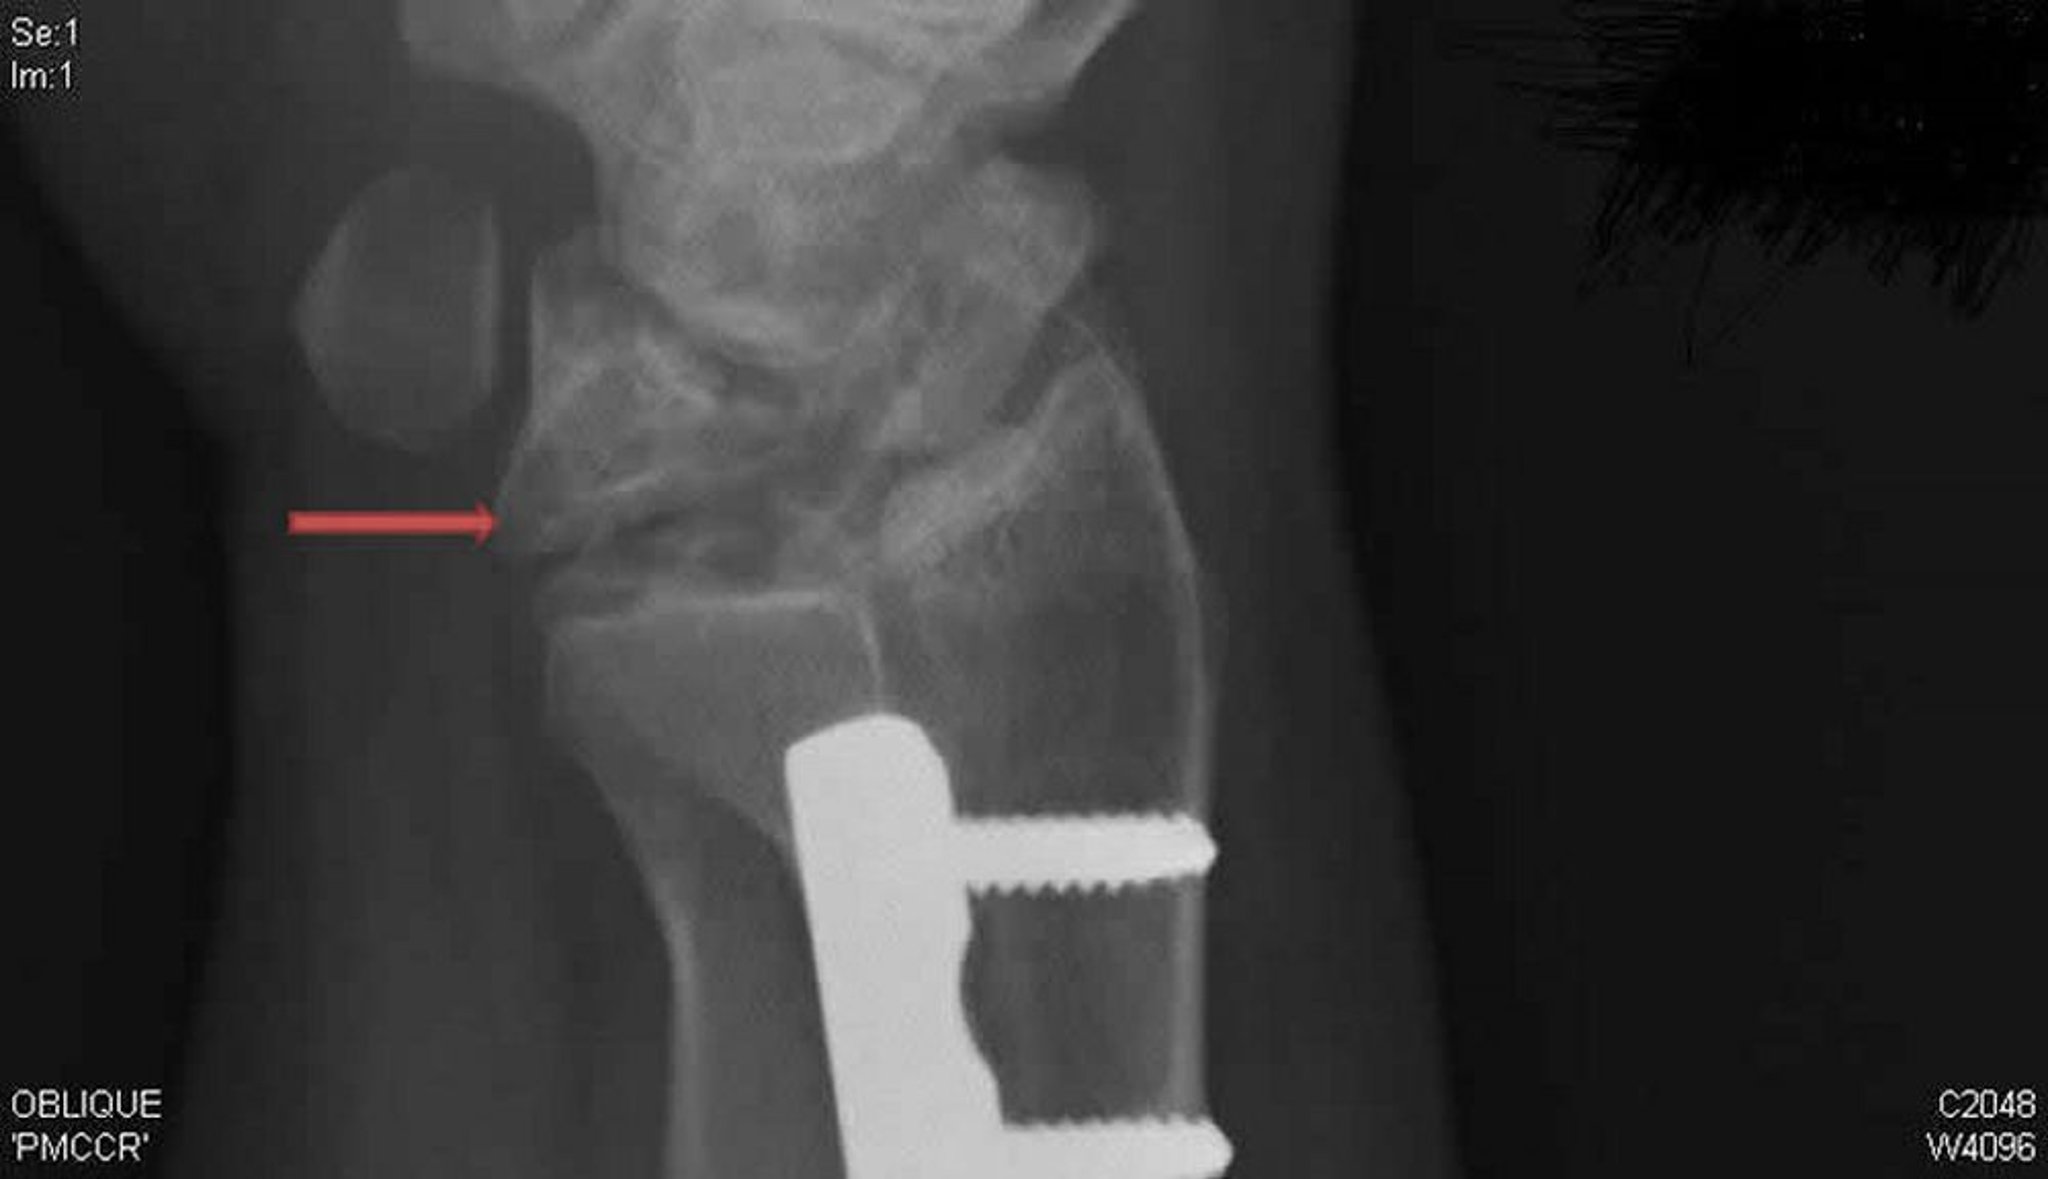

Doença de Kienböck (radiografia em incidência oblíqua)

Essa radiografia oblíqua do punho direito mostra doença de Kienböck. Observar o colapso e a fragmentação do osso semilunar (seta), que não estavam aparentes na incidência posteroanterior.

Radiografia, cortesia de David R. Steinberg, MD.